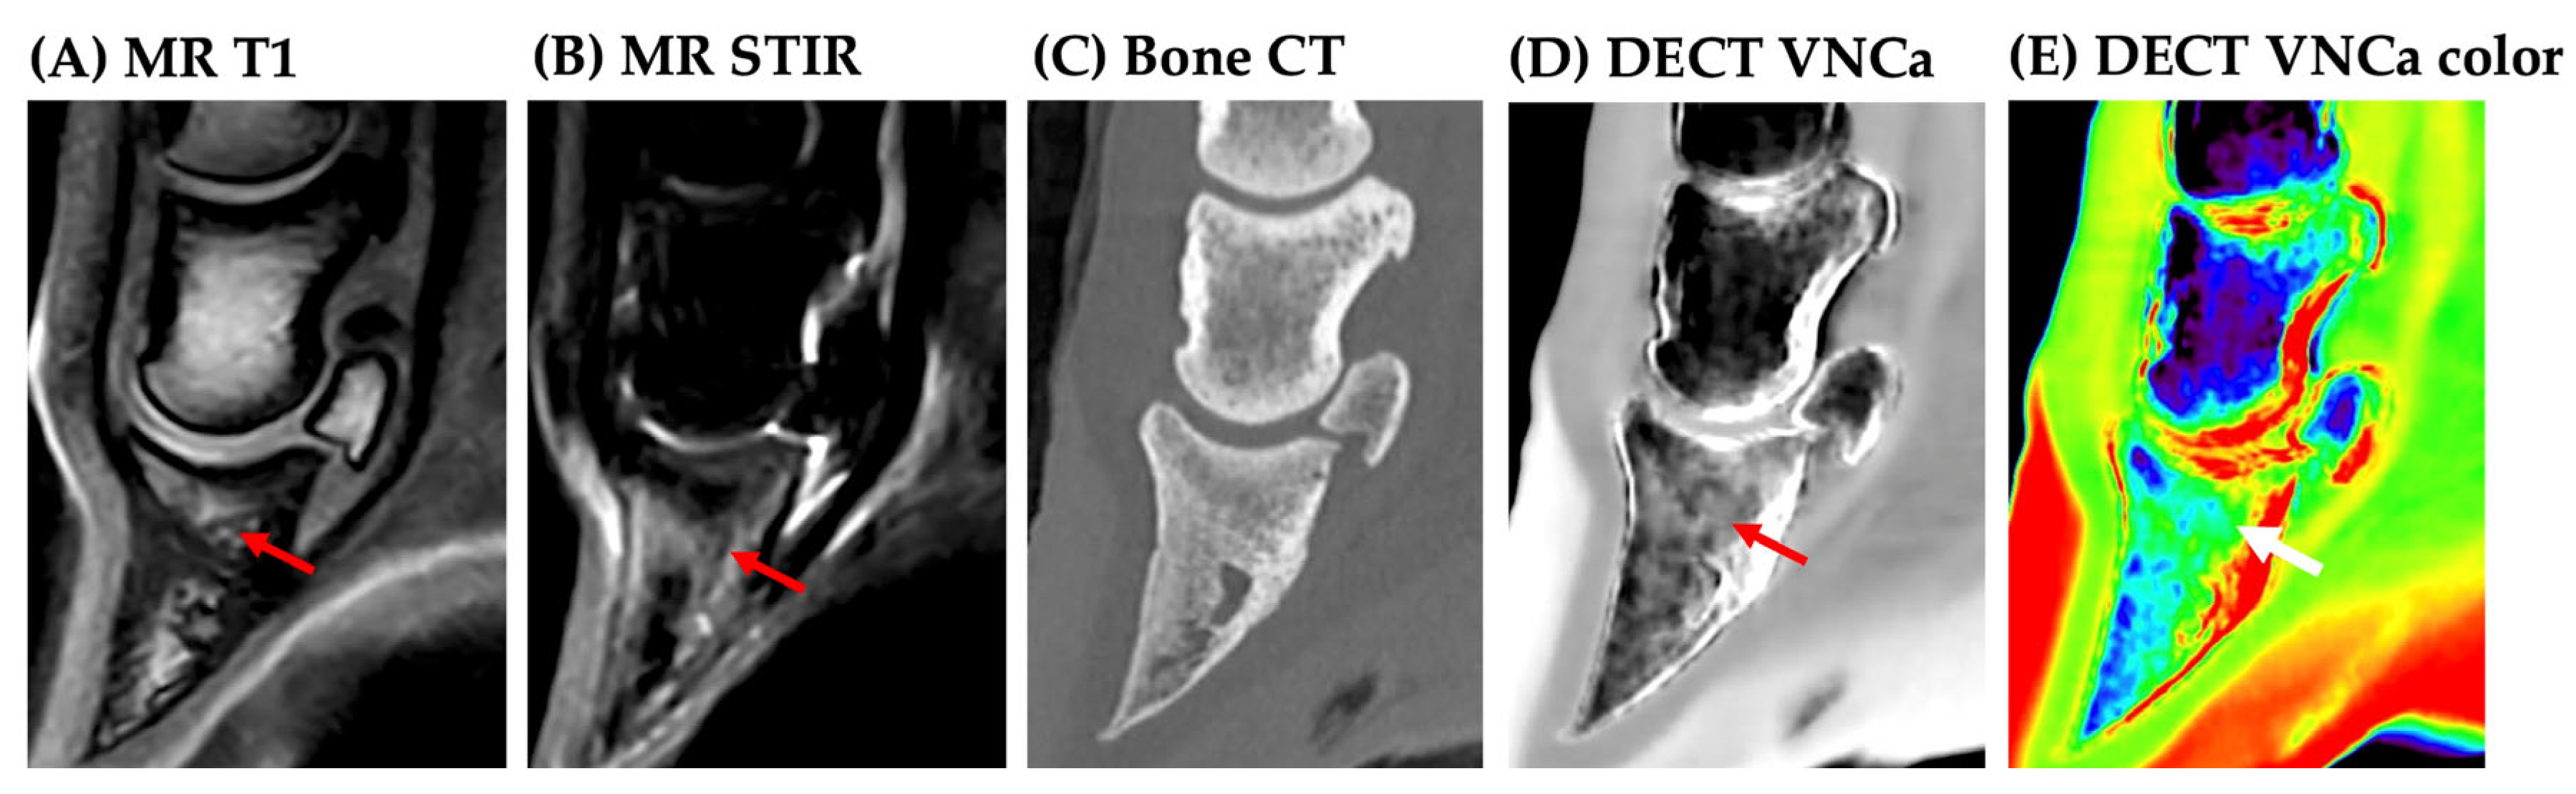

1. Introduction